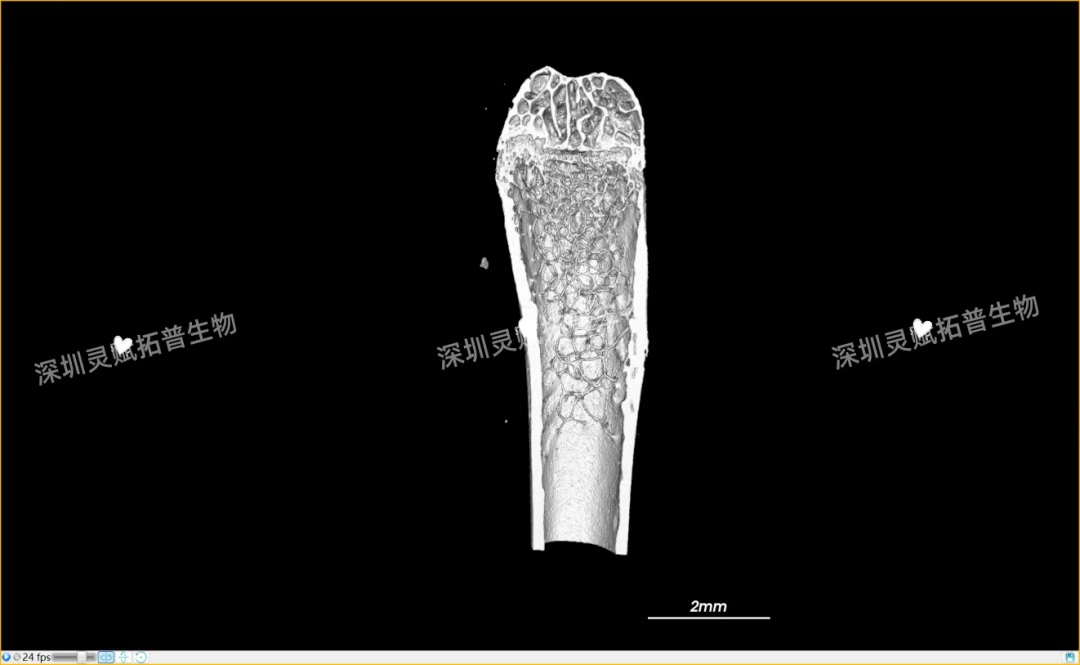

以小鼠股骨检测为代表,带大家直观感受ballbet艾佛森体官网生物的服务实力:

本次实验对 E2 系列(E2-1、E2-2、E2-3)共3个小鼠股骨样本进行标准化扫描,取得了 0.5mm、2mm 等不同尺度的清晰成像,不仅直观呈现了股骨的宏观形态,更精准捕捉到骨小梁排列、皮质骨厚度等微观细节,为后续骨质疏松、骨修复等相关研究给予了可靠的量化数据支撑。

下附E2系列的典型案例:小鼠股骨扫描成像图